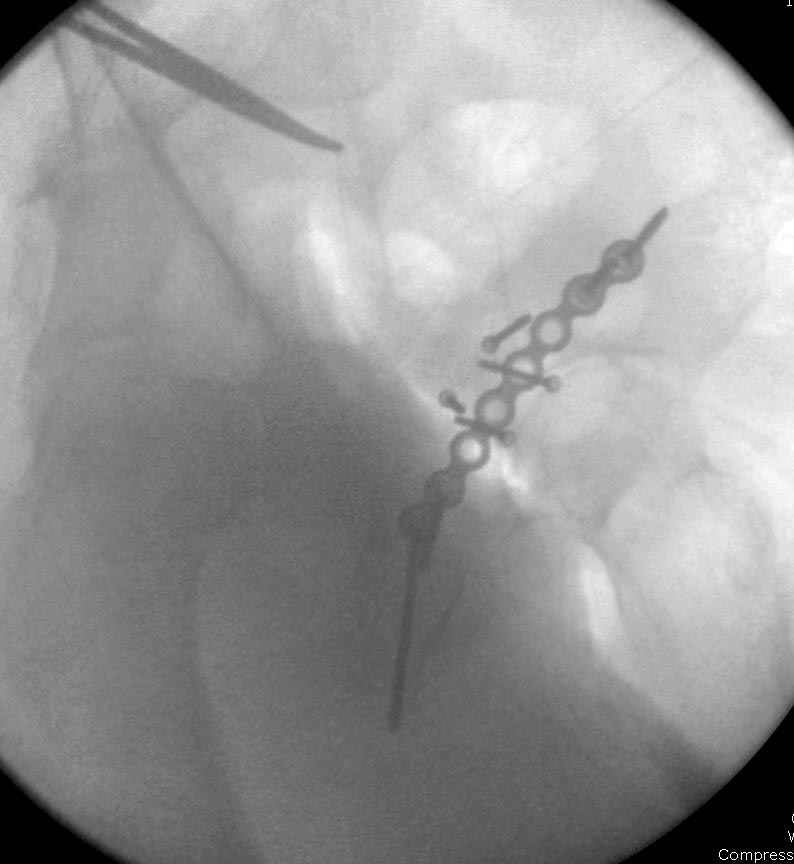

Если, например, доводится лечить больных с псевдартрозами шейки бедра, то надобность есть, и приходится. См. приложение.

На рисунке N1 предоперационный план лечения ложного сустава шейки бедра- линия ложного сустава, угол и направление введения импланта, клиновидная остеотомия в градусах и миллиметрах, второй снимок после коррекции, расчет, на сколько удлиняется конечность и размеры импланта;

N3 рисунок окончательный снимок, после операции моя рентгенограмма должен выглядеть примерно как эта картина. На N4 снимке клин перед удалением; N5 послеоперации 3 нед.; N6 окончательная рентгенограмма.

(доложен в Ст. Петербурге 2003 и в Москве 2004)

варус при проксимальном отделе 95 градусной пластиной.